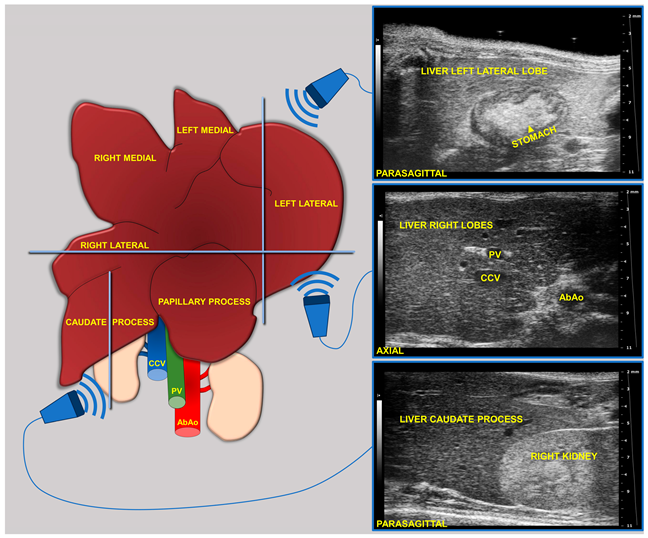

During imaging sessions, body temperature, heart, and breath rates were monitored and normothermia was maintained using a heated platform and an infrared lamp. Mice were anesthetized with inhalant gases (induction chamber: 4% isoflurane plus 2 Lt/min oxygen; maintenance with nose cone: 1.5–1.8% plus 2 Lt/min oxygen). Subsequently, the mice were placed in a supine position and a coupling gel was applied to the trichotomized skin. US two-dimensional (2D) B-mode images of the liver of mice (left, right, and caudate lobes, sagittal and axial planes) at 8 (baseline, pre-diet), 16, and 24 weeks of age were acquired in real time by a veterinary radiologist with 17 years of experience (SG) (

Figure 1). A dedicated HFUS equipment was used (Vevo 2100, FUJIFILM VisualSonics Inc., Toronto, ON, Canada; MS550 transducer: central frequency 40 MHz; focal length 6 mm; depth of penetration 5–15 mm; 30–40 µm axial and 70–90 µm lateral resolution). The time gain compensation and other operating parameters were kept constant throughout experiments (frequency = 40 MHz, frame rate = 16 images/s, gain = 30 dB, depth = 11 mm, width = 13.00 mm, dynamic range = 60 dB, sensitivity = high; transmit power = 100%) to avoid experimental bias. Each liver HFUS acquisition, including overall animal preparation, took no more than 15 min. During recovery, all animals were monitored for any signs of pain or discomfort.